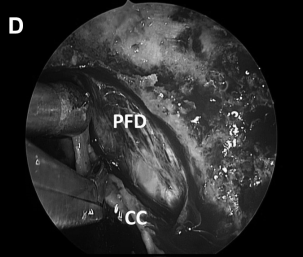

▼解剖、剥离并切除肿瘤包膜(D、E)

▼(L)使用鼻中隔瓣(NSF)完成封闭。CC,囊包膜;PFD,后颅窝硬脑膜;S,蝶鞍;T,肿瘤。

神经内镜手术“动态控制”的重要关键优势是,它允许外科医生逐步靠近目标并放大术野,同时减少鼻腔内手术器械操作之间的冲突。这在某些情况下如重要神经组织的解剖分离、肿瘤暴露中至关重要的,例如在颈内动脉附近钻孔、暴露视神经顶部或在硬膜内分离解剖过程中。此过程类似于在执行更细致的操作时使用显微镜进行放大。例如,在手术操作系列图中,我们可以了解当从骨质解剖分离颈内动脉ICA(A)、从硬脑膜上解剖病变包膜(D)或耳蜗下的骨质时,神经内镜与磨钻头的距离有多近(I)。该技术结合了耳鼻喉科和神经外科手势的优点。